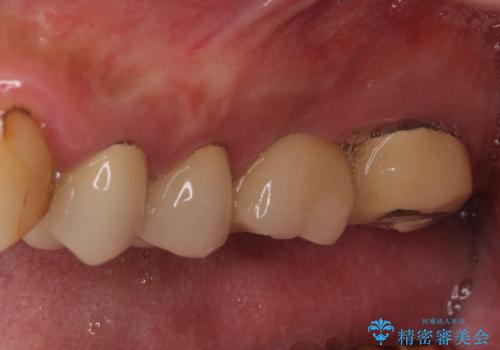

診査の結果、左側は奥歯2本、右側は1本の抜歯が必要であることが分かりました。

左側は大臼歯2本と小臼歯1本が欠損しているため、インプラント2本を治療したブリッジ、右側は中間欠損であり、前後の歯も加療が必要であったためブリッジによる補綴治療を行うこととしました。

抜歯となった歯は全て神経が抜かれた歯であり、強大な咬合力によって破折したことが原因で抜歯となりました。

左右同時に強大な力を受けながらの治療であったため、仮歯の脱落や破損などがひんぱつしました。